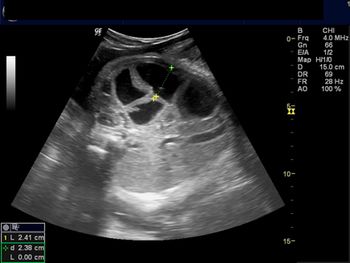

Challenge your diagnostic skills: Can you identify this finding in the fetal abdomen?